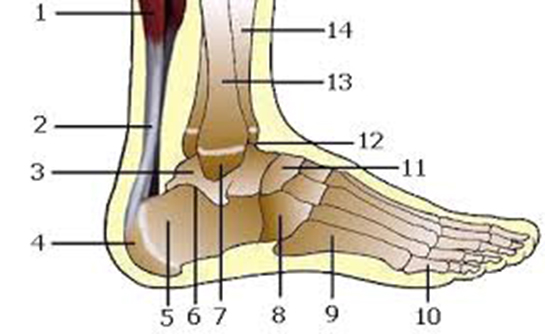

Bu tür yaralanmalar, genellikle ani ve beklenmedik durumlar sonucunda meydana gelir. Yaralanmanın ciddiyeti, kesik alanının derinliğine, kanamanın miktarına ve sinir veya tendonların etkilenip etkilenmediğine göre değişiklik gösterir. Kesilmiş Bilek Tedavi Aşamaları Kesilmiş bilek tedavisi, genellikle üç ana aşamadan oluşur: acil müdahale, cerrahi onarım ve rehabilitasyon.